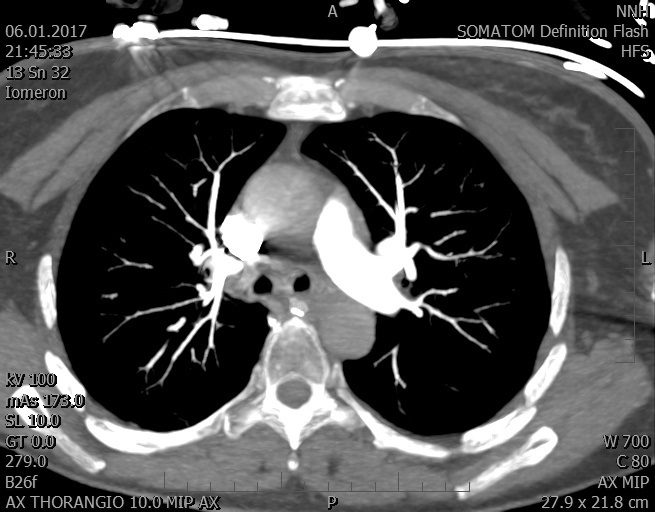

Video 2 - Echokardiograficky byla zjištěna těžká dysfunkce dilatační levé komory s nezvětšenou pravou komorou.Pro nejasnou příčinu zástavy jsme provedli i vyšetření výpočetní tomografií (CT), které vyloučilo plicní embolizaci (série 1 - soubory na konci článku). V den přijetí při přetrvávající oběhové nestabilitě byla nemocná opakovaně defibrilována pro fibrilaci komor se stabilizací rytmu po podání amiodaronu a mesocainu. Dle hemodynamických měření se jednalo o těžký kombinovaný šok. Vstupní laboratorní vyšetření bylo bez větších pozoruhodností. Posléze jsme doplnili anamnézu od příbuzných a zjistili, že pacientka užila do dvou hodin před srdeční zástavou první tabletu amoxicilinu na lehký respirační infekt. Při nevýtěžnosti vstupních vyšetření a nových anamnestických informacích jsme doplnili 14 hodin po kolapsu vyšetření koncentrace tryptázy v séru, která byla extrémně zvýšena (tabulka 2), což nás vedlo k podezření na anafylaxi.